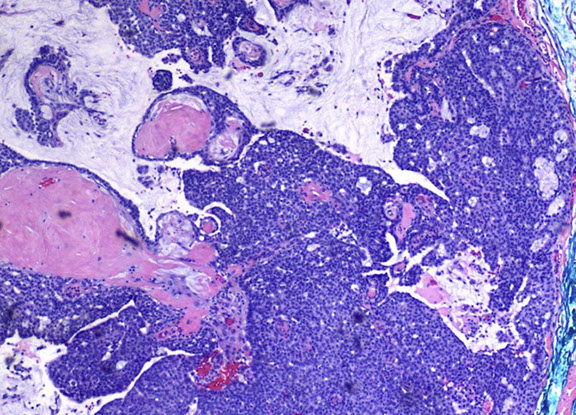

Pilomatrixoma

Trichohyaline granule (which are usually seen in hair shafts) in a pilomatrixoma

- aka calcifying epithelioma of Malherbe

solitary, bluish, firm (often calcifies), benign subepidermal spherical nodule

b9 hair follicle tumor

MC on face of kids or young adults

- 75% of childhood adnexal tumors

- can have multiple lesions in myotonic dystrophy

Sharply circumscribed cyst-like structure in dermis, possibly contiguous with hair follicle (may arise from hair matrix)

- can have inc mits (the malignant form is rare and usually very atypical)

- may have trichohyaline granules (which are usually seen in hair shafts)

3 cell types in fragmented cyst wall:

1) outer layer of blue (basophilic) basaloid martical cells with round nuclei and scant cytoplasm which dies and become dead keratin, which are the ghost cells

- imitate the cells in the root, or bulb of a normal hair follicle

2) mixed zone of eosinophilic cells c large round vesiculated nuclei

3) central zone sheets of keratinized pink "ghost" or "shadow" cells c distinct cell borders and central unstained nuclei

- difference from BCC: basaloid cells undergo abrupt keratinization and form "ghost" cells

Has foci of foreign body reaction, calcifications and ossification in shadow cell lobules

See melanin in shadow cells

Fibrotic stroma infiltrated with granulomatous inflam

Solid nests of basaloid cells may cause misdiagnosis of BCC

Ddx: Basal cell carcinoma c matrical differentiation (differs by continuity with epidermis and abrupt transition into shadow cells without the eosinophilic zone)